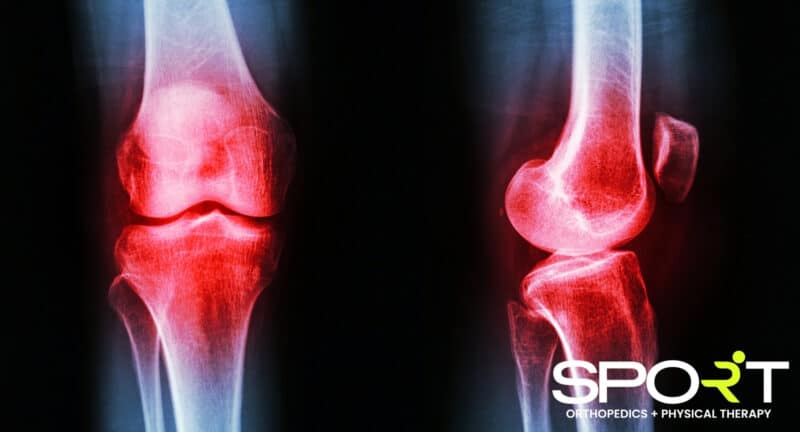

Your doctor diagnoses an unstable kneecap during a physical exam. They will flex your hurt knee and press the area surrounding your kneecap. They take x-rays of the knee to see where it fits into the trochlear groove. These images also show any additional bone injuries.